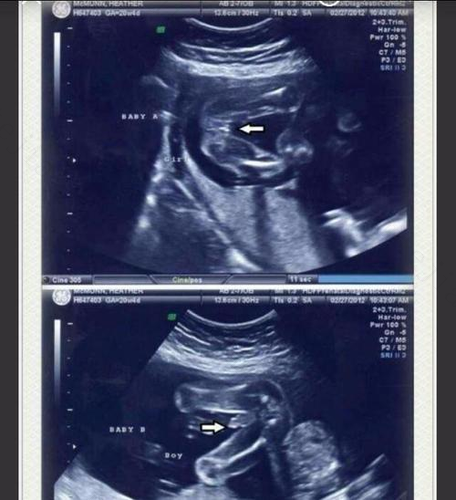

判断胎儿男女准确方法(图片来源网络)